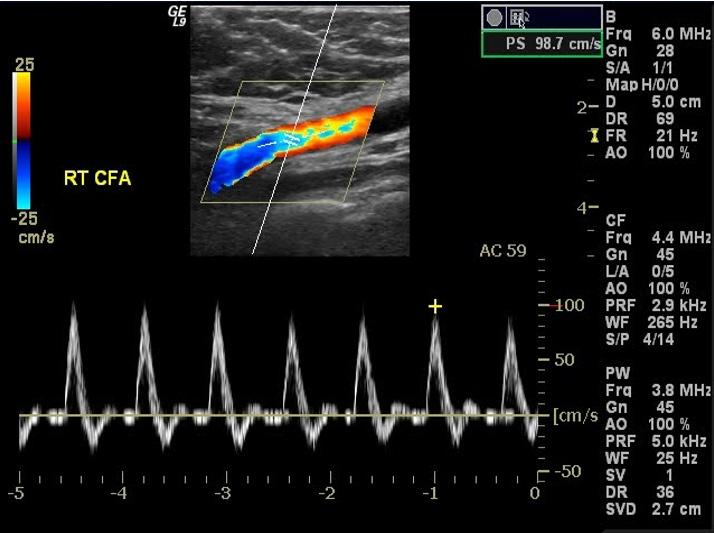

Ecografía doppler o de compresión

♦ Prueba de elección (ideal) para confirmar el diagnóstico

♦ Indicaciones

Para probabilidad intermedia o alta (Wells ≥ 1)

– Probabilidad baja (Wells = 0) con dímero D positivo

♦ Resultados

Positivo: confirma TVP

– No compresibilidad de la vena obstruida (hallazgo + importante)

Masa intraluminal hiperecoico (trombo)

– Distensión de la vena afectada

Aumento inadecuado del flujo venoso en la compresión distal de la pantorrilla o maniobra de Valsalva